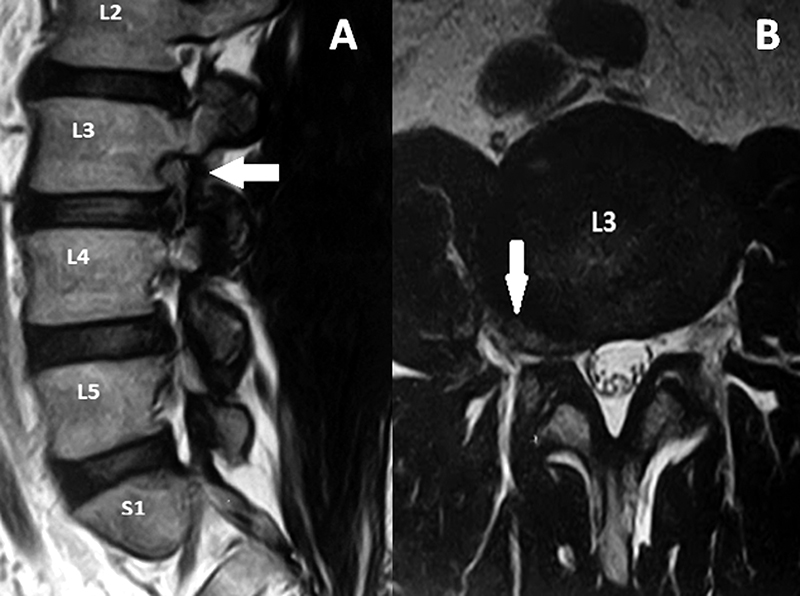

Paciente masculino, de 54 años de edad con dolor crural derecha y parestesias en igual región de tres semanas de evolución con escasa respuesta al tratamiento médico. Al examen físico, presentó paresia del cuádriceps derecho e hipoestesia en cara anterior del muslo y dolor según EVA=9. En RM se observa protrusión discal extraforaminal derecha en nivel L3-L4 (fig. 2). Se propuso una discectomía mínimamente invasiva mediante sistema tubular y microscopio. Se observó una mejoría en 8 puntos en la EVA (Video 1).

Figura 2: RM sagital y axial del caso ilustrativo.